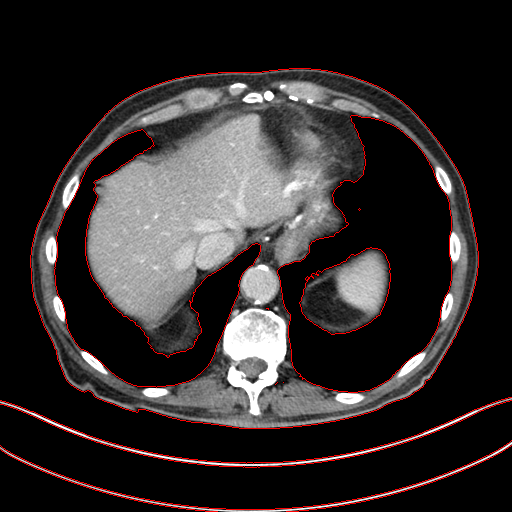

Figure 6: Result of denoising for comparison. We have shown an example of denoising performance on image taken from the 2016 NIH-AAPM-Mayo Clinic Grand Challenge dataset. The display window is [140140-140, 260] HU for better visualization of low attenuated lesion. Readers are requested to zoom in for better view.

As shown in Table 3, DIP has exhibited the worst performance among all the methods. On the other hand, the ConsensusNet yielded a better FID and TML than BM3D but a lower PSNR and SSIM than other methods. The ConsensusNet divided the original projection data of the low dose CT image into two subgroups and back-projected to create the noisy input signal. Consequently, the noisy input image is much noisier than the original LDCT image. Also, the structural loss occurred during the generation of noisy images, so as a result, the PSNR and SSIM of this method are lower than other methods. Texture matching loss (TML) is used to measure the texture difference between the reconstructed and original images. The lower value of TML indicates that the generated texture is similar to the original. In comparison, FID estimates the distance between the distribution of the generated image and real images. A lower value of FID signifies the generated images are more similar to the original image. The current deep learning era demands a denoised image with a low value of these metrics. These denoised images may be used as input for other image classification tasks or segmentation networks. In this regard, the ConsensusNet is superior to the BM3D because it uses the deep neural network’s expression power. CycleGAN is another powerful unsupervised method for image-to-image translation; it achieved better performance than the other methods. However, CycleGAN has a lot of bottlenecks, e.g., longer training time, computation power, hyper-parameter tuning, etc. All these bottlenecks make CycleGAN ill-suited for practical deployment. Meanwhile, our proposed method has achieved the highest PSNR, SSIM, FID, and VIF among all the other methods. Next, we compare the result of denoising visually in Figure 6. It can be observed that the proposed method performs significantly better than the other unsupervised methods. BM3D output produced a blurry denoised image and contained many splotchy artifacts. The same blurriness can be observed in the output of ConsensusNet, and DIP, although noise suppression is adequate, and splotchy artifact is absent. In the output of CycleGAN, we can observe the presence of residual noise, especially in the high noise regions. Next, we identified one low attenuated lesion in the sample image and marked the lesion with a red colour bounding box. The zoomed view of the region inside the bounding box is given in Figure 7. In our method’s output image, the lesion’s visibility is enhanced significantly than in other methods. Despite being an unsupervised method, the visibility of the lesion is comparable with the original NDCT image. Also, from the zoomed view, we can perceive that our method has suppressed the granular pattern without losing the original image’s texture.